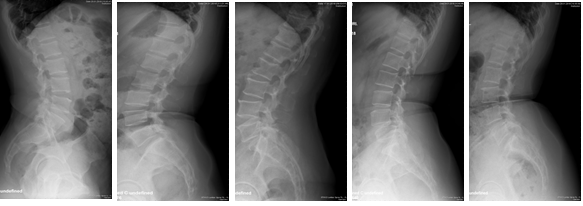

In the medical era, health of a bone is accessed by the bone mineral density (BMD) test. Bone fracture risk in the humans are estimated or evaluated by the BMD test. The test statement recognizes the presence of signs of presence of the frequent occurring disease in the bone called as osteoporosis. So it is obligatory to enclose a customary database in X-Ray images for the young bud researchers to capture up the dealings to the advance stage by accurate examination of the medical results of the images. The projected X-Ray database is termed XSITRAY, characterizes an early attempt to offer a group of X-Ray images of Spine, Femur, Clavicle, Extremity & Ankle, Extremity & Hand and Knee bones. The details such as age, gender and unique Id of the patient are interpreted in the database.

In this database, for every image, Annotation is provided for following attributes: age, gender and unique Id of the patient.

Fathima S. M. N, Tamilselvi R, Beham M. P. XSITRAY: A Database for the Detection of Osteoporosis Condition. Biomedical & Pharmacology Journal, March 2019; 12(1). DOI: http://dx.doi.org/10.13005/bpj/1637